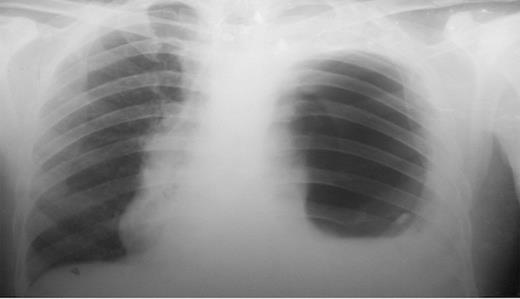

A 32 year old male was admitted to the emergency department with a history of nausea, vomiting, pain in the chest and upper abdomen as well as breathlessness of 3 days duration. He had a history of blunt trauma to the abdomen following a fall from a tree 4 years previously. He was then treated conservatively and no diaphragmatic hernia was detected. On physical examination the patient appeared pale, dehydrated and had dyspnea. Examination of the left chest showed decreased movement on respiration, absent breath sounds, bowel sounds were present and dullness on percussion. Apart from a mild anaemia (9gm/dl), all blood tests were within normal limits. The chest X-ray showed a large air-fluid level in the left thoracic cavity with a nasogastric tube within it, collapse of left lung field, obliteration of cardio-phrenic angle and shifting of the mediastinum toward the right side. (Figure 1)